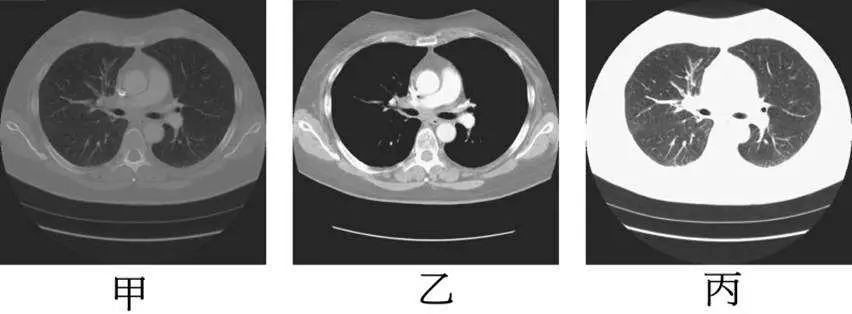

題目提供同一軸切面胸部 CT 影像,以三種不同視窗設定顯示,分別標示為「甲」、「乙」、「丙」:

甲(左圖):整體呈現均勻中灰色調,對比度低,肺臟、縱膈(mediastinum)、骨骼結構間的密度差異不明顯,所有組織趨向相近的灰階值。這是**視窗寬度最大(widest WW)**的典型表現——當 WW 極寬(如骨骼視窗 WW 約 1800 HU),大量不同密度的組織被壓縮到相近的灰階,導致整體對比下降。

乙(中圖):對比度適中,縱膈結構(心臟、大血管)與胸壁軟組織界線清晰,肺實質可見,肋骨骨皮質可辨識。符合標準軟組織或縱膈視窗(WW 約 350–400 HU,WL 約 40–50 HU)的外觀。

丙(右圖):影像整體非常明亮(趨近白色),肺紋理清晰可見,肺血管呈黑色條紋,縱膈區域顯示為大面積白色。這是**視窗水平最低(lowest WL)**的典型